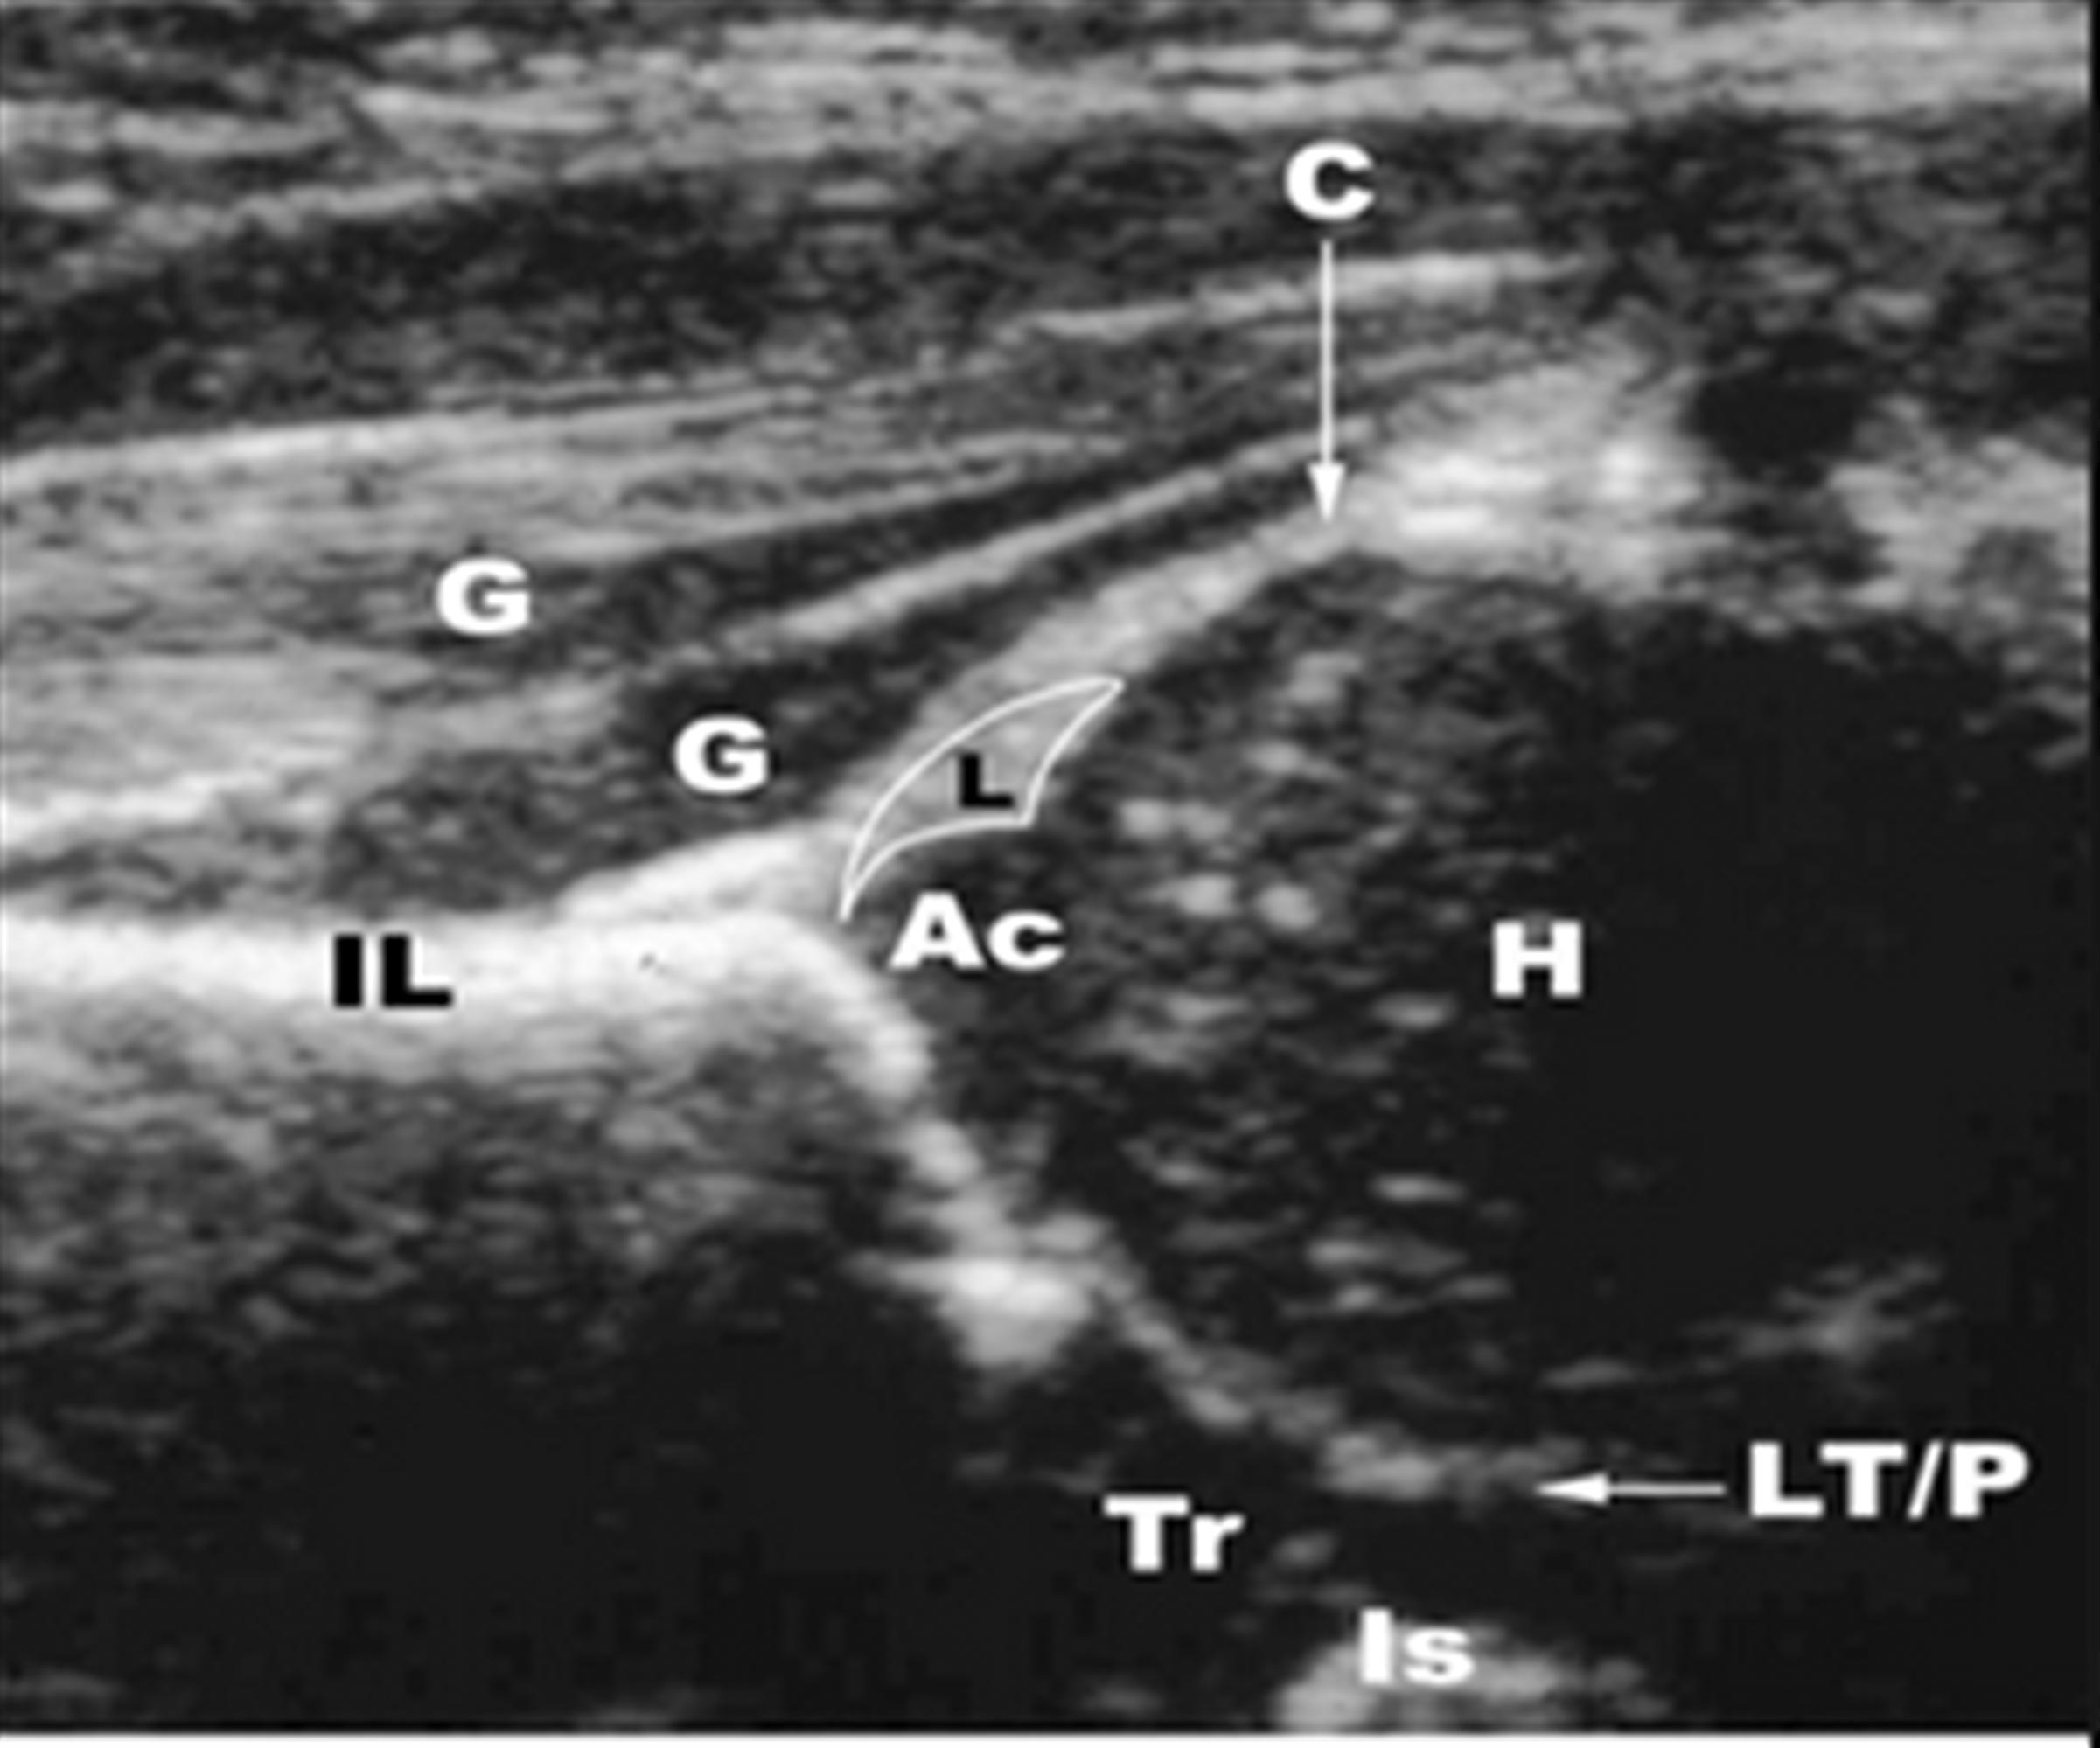

Rupture Of Ligamentum Teres Is Usually Associated With Dislocation Of The Hip.

Interestingly, the presence of ligamentum teres tears were correlated with increased labral tear size and higher grade chondral damage (p=0.005) than those with.

In Persistent Hip Dislocation, The Ligamentum Teres Lengthens And Hypertrophies And Can Block Concentric Femoral Head Reduction.